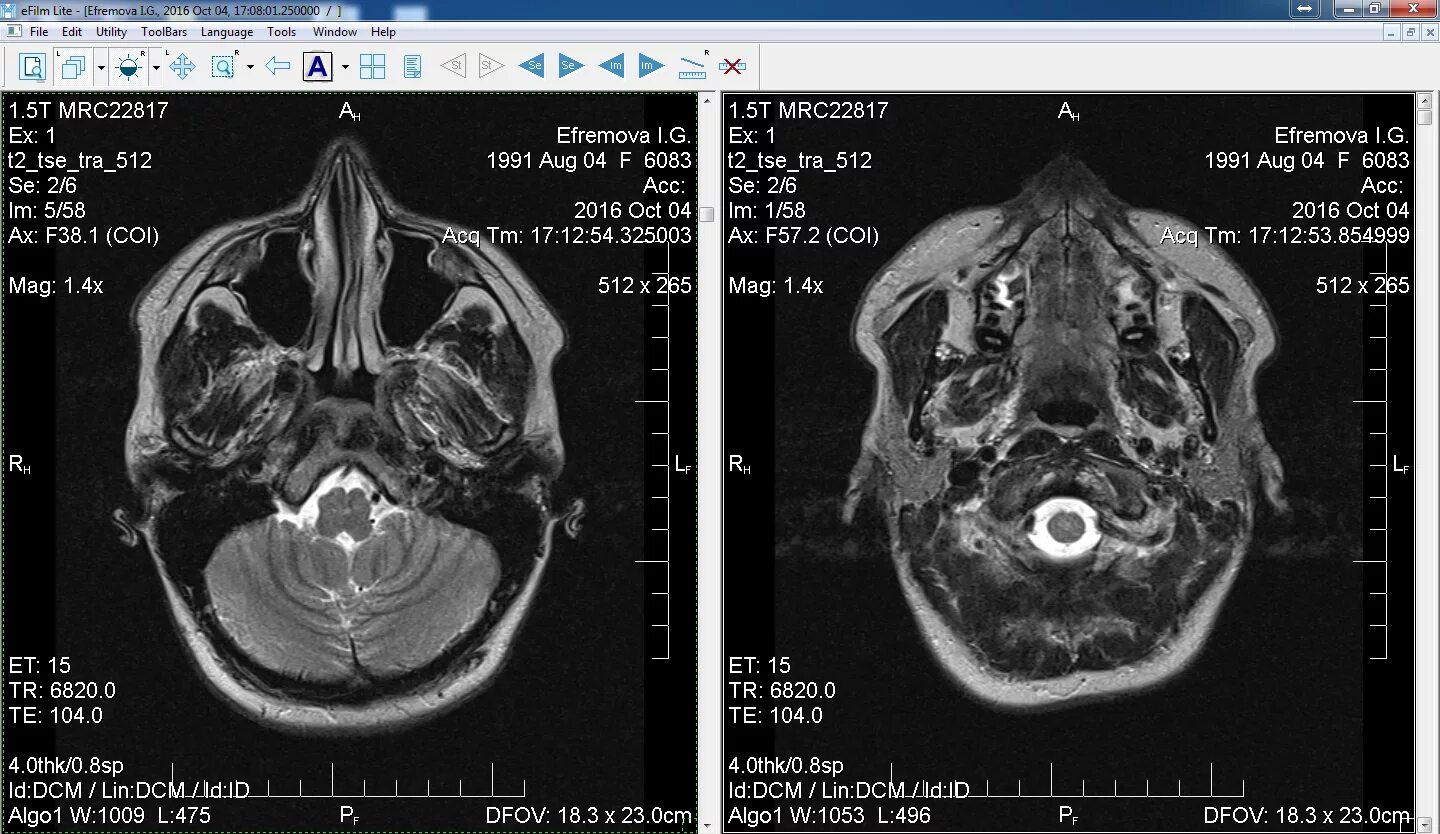

Программа для открытия кт